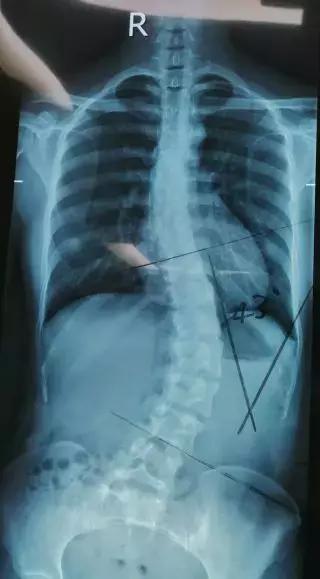

众所周知,正常人的脊柱是一条直线,而陈小姐的背,弯的有多严重呢?

从X光片看过去,大概是这样的。